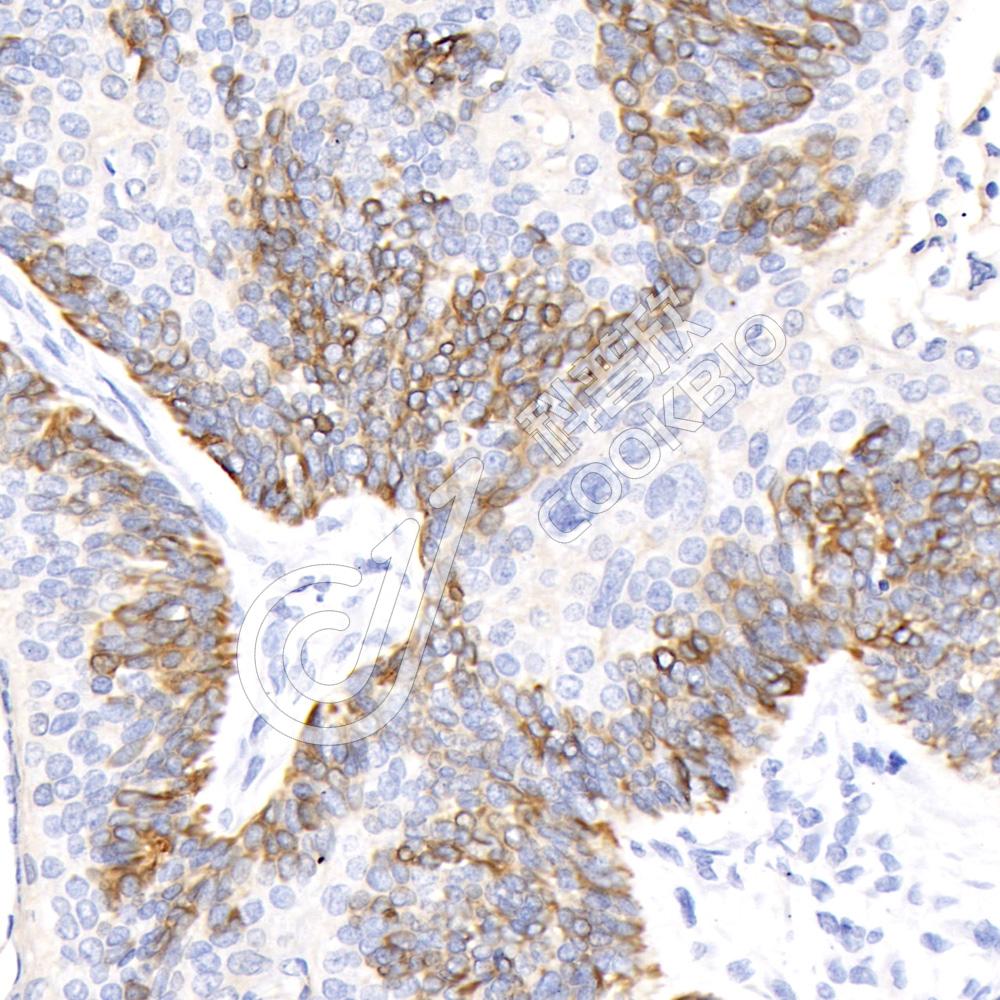

IHC检测POM121蛋白(货号 K1341052).

样品: 人宫颈鳞状细胞癌群, 4%多聚甲醛 (货号KSG1101) 固定12-24小时.

抗原修复: 柠檬酸抗原修复液(干粉, pH 6.0) (KSG1201), 98℃, 20分钟.

—抗: 1: 300稀释, 4℃ 孵育过夜.

二抗: S-vision免疫组化多聚二抗(山羊抗兔),即用型 (货号KB3906), 室温孵育20分钟.

样品: 人喉癌, 4%多聚甲醛 (货号KSG1101) 固定12-24小时.